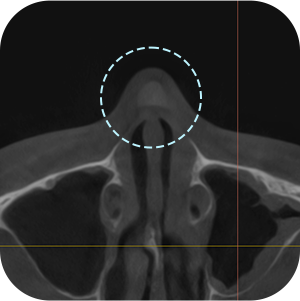

以前、手術の 保形物情報確認

鼻中隔湾曲症など 機能的問題確認

現在の保形物の 位置確認

鼻のCT撮影、どうしても必要ですか?

A再手術ですので、もっと精密に診断する必要があります。

内部の機能的な問題を正確に診断することで

安全な手術が可能となります。

鼻再手術は徹底した分析が重要です。

3D-CTを通じて正確な分析が

できるから! - 03